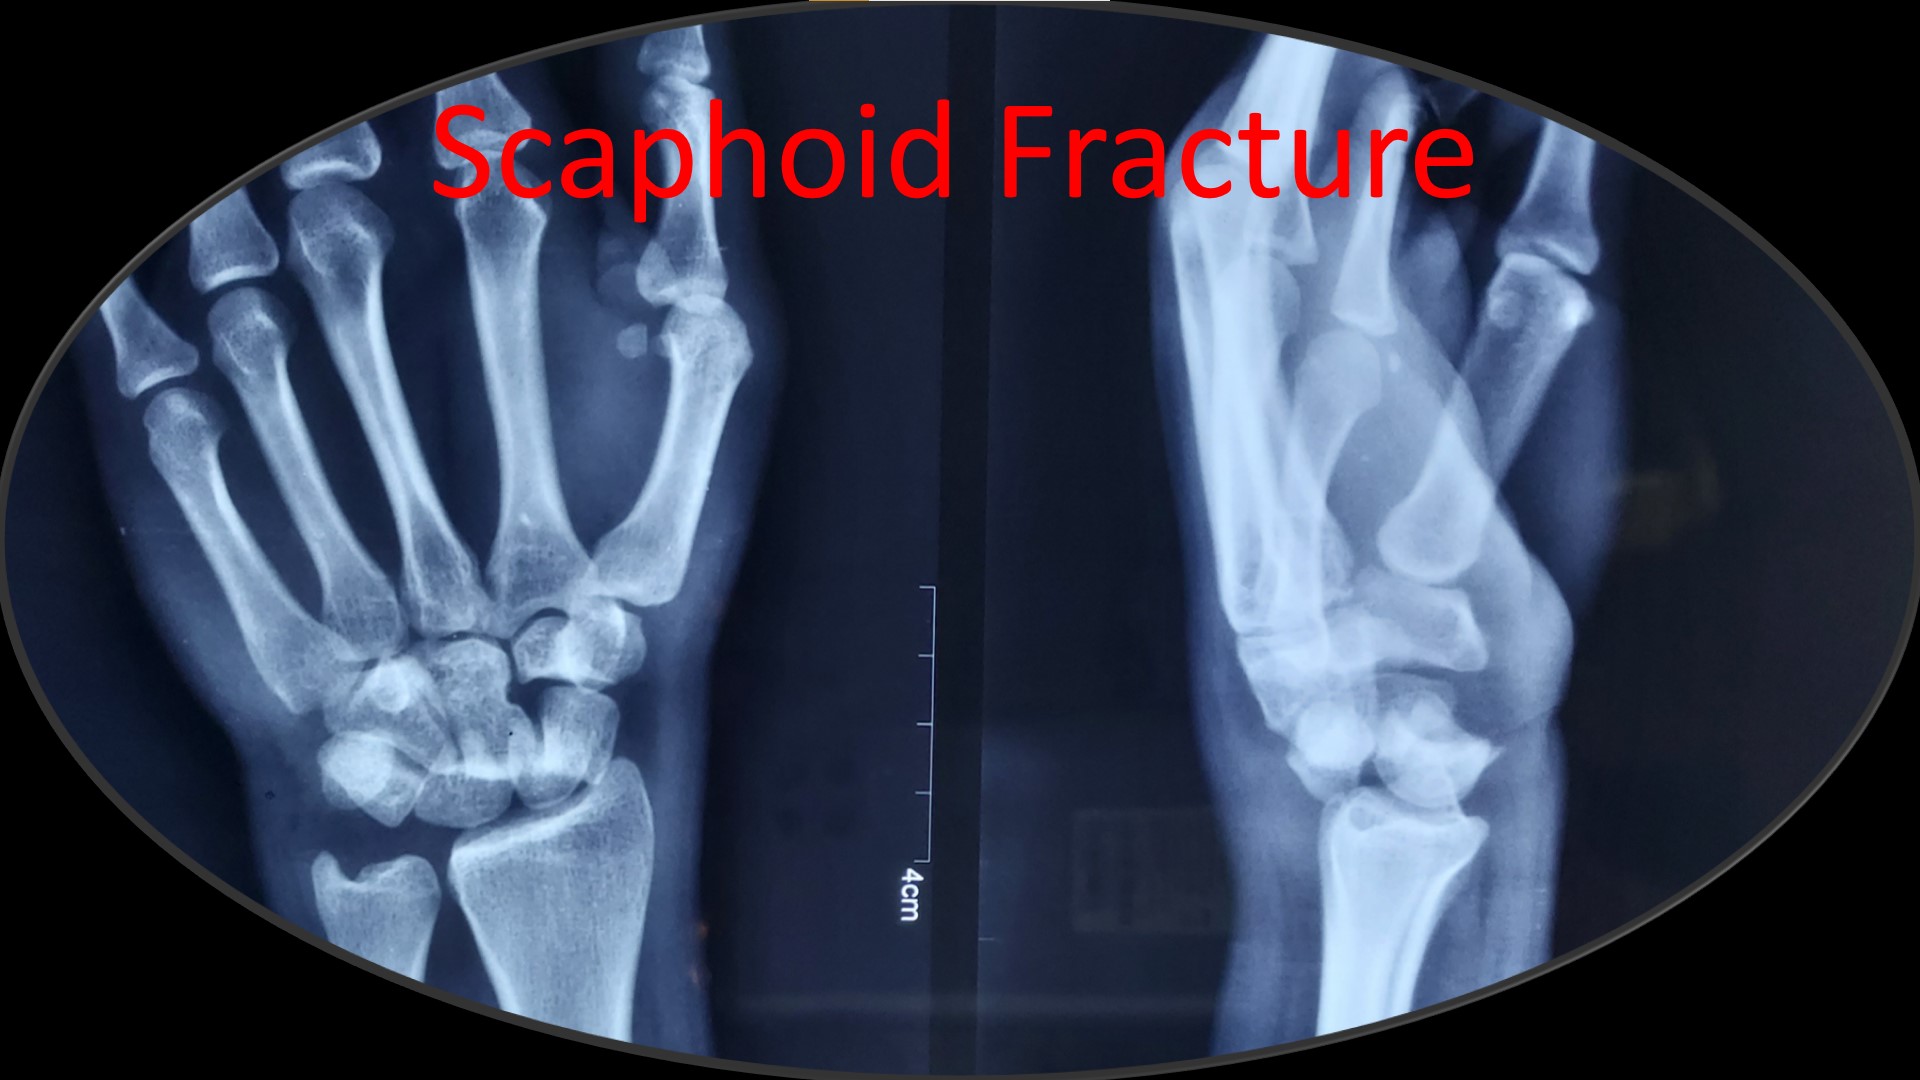

CRPP ( Closed Reduction Percutaneous Pinning )

• Most of the metaphyseal fractures of both upper and lower limbs can be successfully treated by CRPP.

• It can be applied to any intraarticular fractures, distal end radius, elbow, ankle and foot.

·        A Novel Method of Closed Reduction and Percutaneous Pinning with Six K-wires for Intra-articular Fractures of the Distal Radius. Anilkumar Vidyadharan, MBBS, D. Ortho, JAAOS Global Research & Reviews (June 2020-volume-4-issue 6)